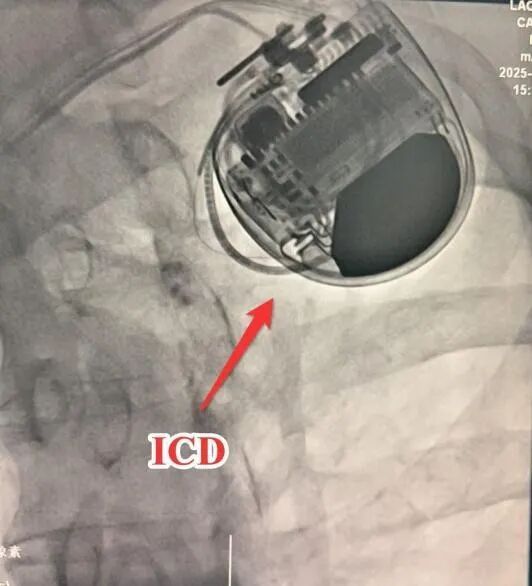

此时,植入ICD(植入型心律转复除颤器)成为预防猝死的关键选择,却面临两难境地:一方面,患者因支架植入需长期服用抗血栓药物,此时进行ICD植入手术,将显著增加伤口出血、血肿感染甚至心内膜炎的风险;另一方面,若不植入ICD,患者将持续暴露在随时可能猝死的高风险中。

面对这一临床困境,心内科团队经过全面评估,最终决定迎难而上。在马江伟主任的亲自操作下,手术团队在术中实施精细的止血处理,成功完成ICD植入。术后一周,康先生恢复平稳,未再出现心衰症状,日常活动无不适,真正转危为安,顺利出院。